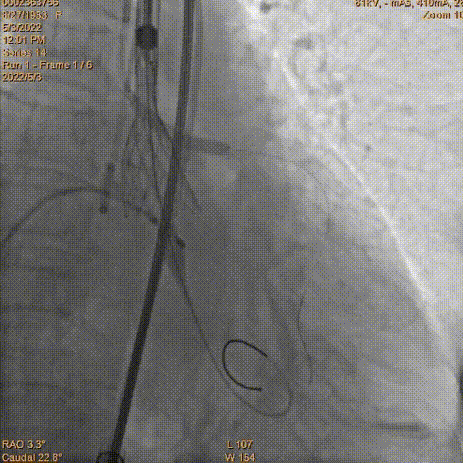

工作位冠脉球扩

瓣膜释放2/3同时发现患者血压降低,立即释放冠脉支架

瓣膜脱钩

AV23瓣膜完全释放

术中TaurusElite瓣膜系统优异的输送性能,保障了术中轻松过弓、顺利跨瓣。钟志雄院长团队通力配合、精准释放,充分利用TaurusElite可回收功能,在瓣膜释放至2/3时,多角度评估瓣膜植入深度、锚定力以及冠脉灌注情况。此时患者血压偏低,根部造影评估后,考虑左主干开口受限冠脉灌注不全导致。随即释放预埋支架,行烟囱支架技术保护冠脉。完成冠脉保护后,确认瓣膜植入深度合适、锚定力稳定,故缓慢逐个脱钩,进行瓣膜释放。